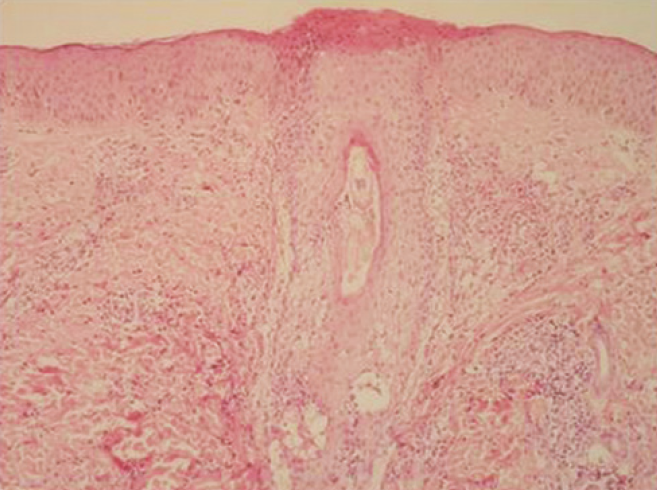

¿HISTOPATOLOGÍA QUE SE OBSERVA EN LA FOLICULITIS?

A

SE OBSERVA UN INFILTRADO INFLAMATORIO PERIFOLICULAR SUPERFICIAL Y PROFUNDO (FIG. 73-8).